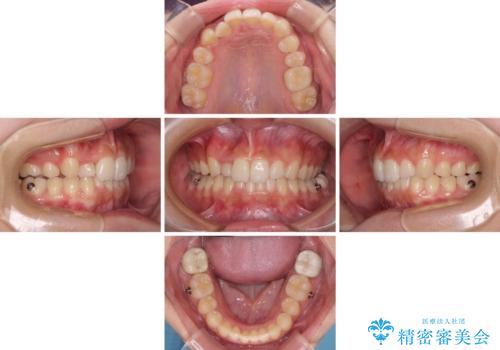

インビザライン単体での治療は困難と判断し、補助装置により八重歯移動後にインビザラインを用いることとしました。

インビザラインでは治療期間が延びることが予想されたため、ワイヤー矯正を提案しましたが、セラミッククラウンが多く、壊すあるいは傷が付く可能性があることから、長期間であってもインビザラインを選択されました。